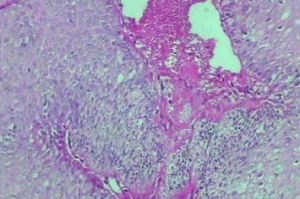

目前認為Barret食管系先天性食管上皮發育異常或是長期反流的結果,故對具有非心源性胸骨後疼痛,反酸,吞咽痛或/和吞咽困難等症狀者應儘早行吞鋇X線檢查及食管鏡檢查,X線鋇餐檢查可了解有無食管潰瘍及食管裂孔疝等反流性疾病存在。內窺鏡系確診手段,注意有無齒狀線消失或上移,橙紅或鮮紅色柱狀上皮黏膜區呈島狀分布及有無並發潰瘍、狹窄等,鏡下取材活檢可鑑別系鱗狀還是柱狀上皮。